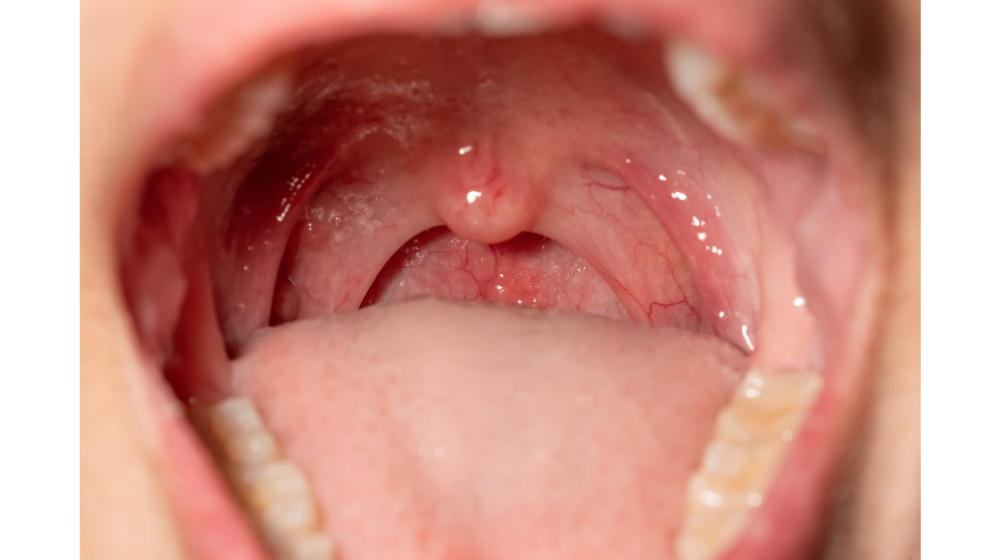

ヘルパンギーナ 喉だけ (226 無料画像)

ヘルパンギーナ写真で見る「子どもの病気」 - みやけ内科・循環器科 総合内科のアプローチ。